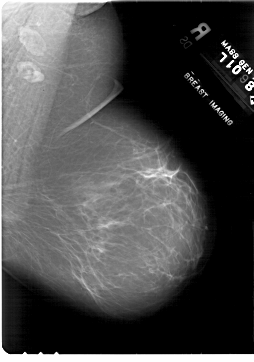

A_1818_1.RIGHT_MLO

RIGHT_MLO LINES 6871 PIXELS_PER_LINE 4816 BITS_PER_PIXEL 12 RESOLUTION 43.5 NON_OVERLAY